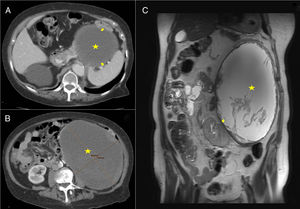

Our patient is an 84-year-old woman with a history of lumbar pain radiating toward the flank and hypogastrium associated with a palpable abdominal mass that had been increasing in size for the previous 8 years. On physical examination, the abdomen was soft and a mass was observed in the left hemiabdomen extending from the subcostal region to the left iliac fossa; the mass had smooth edges, and palpation was not painful. Blood count, biochemistry and hormone function tests showed no noticeable alterations. A computed tomography (CT) scan revealed a large mass in the left hemiabdomen (caudal and medial to the splenic angle of the colon) that was predominantly cystic and measured 20×14.5×19.5cm (Fig. 1A and B). Magnetic resonance imaging (MRI) detected a large retroperitoneal mass that occupied the entire left flank, showing liquid content (Fig. 1C), whose origin could not be specified. Given the large size of the tumor, the patient's symptoms and the need for classification, we decided to operate.

(A and B) CT: cystic mass (marked with a star) compressing and displacing the spleen, colon and left kidney (arrows). (C) MRI-T2: mass with liquid content and heterogeneous internal material (marked with a star); the walls present an irregular morphology and increased thickness, displacing the left kidney downwards and internally (arrow).